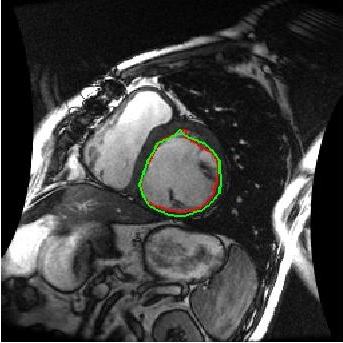

We train our ISR network from scratch. Each volume slice is treated as a separate image and transformed by random rotation and translation. We rotate the images between in steps of . For each rotation we translate the image by pixels in steps of . Thus on an average we get transformation for each image. Thus an average of slices per image gives a total of cardiac MR images. We show results on ISR for scale factor . Results for ISR are summarized in Tables 5. Following the approach for retinal landmark and pathology segmentation, we also show results for cardiac left ventricle segmentation (Table 6). For each segmentation approach we employ UNets as the segmentation framework and show results for different super-resolution methods as well as the low-resolution images (). Dice metric values for segmentation accuracy are shown in each case. Similar to retinal pathology segmentation we extract a patch covering the pathology and apply super-resolution for scale factors .

Figure 6 shows results for segmenting the cardiac LV from MRI. For each case we present results on the original HR images, SR images obtained by each of the methods being compared and also when using the LR images (scale factor ). It is quite obvious that the LR images are very fuzzy and don’t give accurate information on the anatomical boundaries. On the other hand the SR images from our method can predict a highly accurate reconstruction of the actual image. Other ISR methods show some degree of blur in the SR images. It is remarkable that deep neural network based methods are able to reconstruct original high quality images despite limited information in LR images. This is possible because of the ability of the generator networks to learn the relation between HR and LR images.